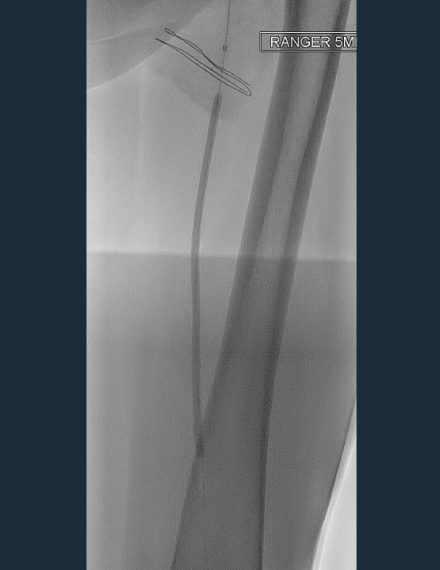

DCB Treatment

Superficial femoral artery (SFA) and popliteal artery presenting some fibrotic plaque were treated with 5.0 mm plain old balloon angioplasty (POBA) and drug-coated balloon (DCB) to improve flow. -